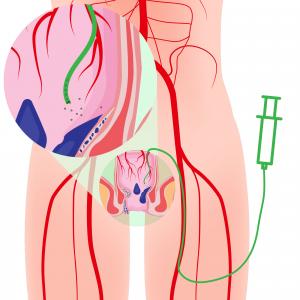

On the other hand, the HAE procedure is performed entirely within the body’s vascular system. An interventional radiologist uses imaging to guide a catheter from a tiny entry site in the wrist or thigh to the hemorrhoid. Special coils and/or sclerosing agents are then injected to cut off the blood supply to the hemorrhoid, causing it to shrink and symptoms to abate. It is safe and effective (4), with a success rate of greater than 90% (5).